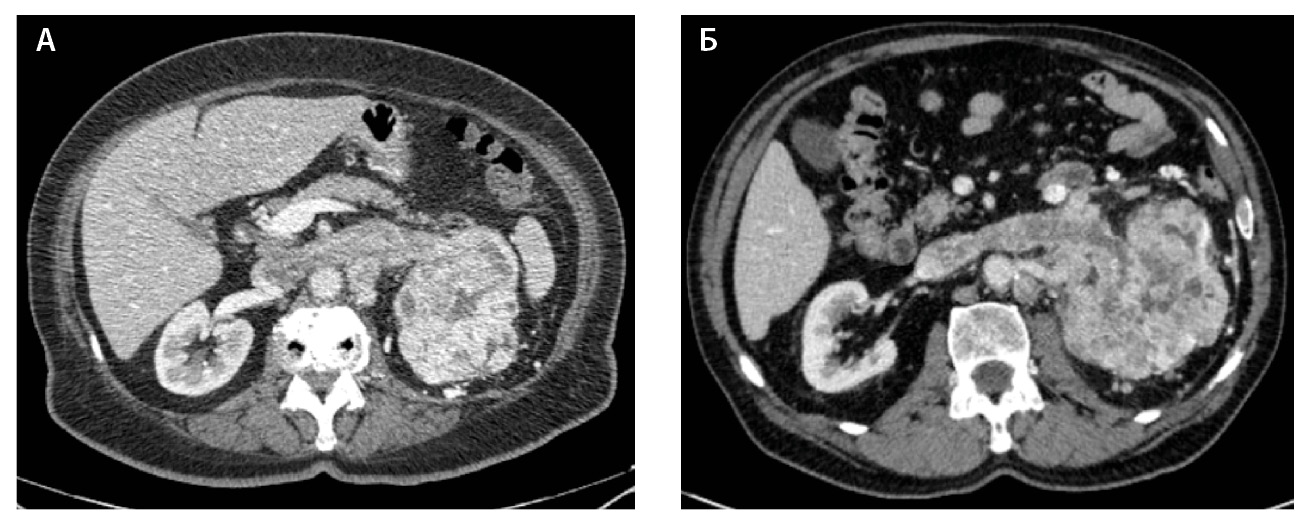

С целью минимизации эффекта цифрового шума и улучшения воспроизводимости текстурных характеристик после формирования ROI применялся фильтр Gaussian Laplacian с условиями Reflect, Periodic, Edge для каждой выделенной зоны интереса. Рабочий процесс показан на рис. 3.

Рис. 3. Рабочий процесс; КТ – компьютерная томография